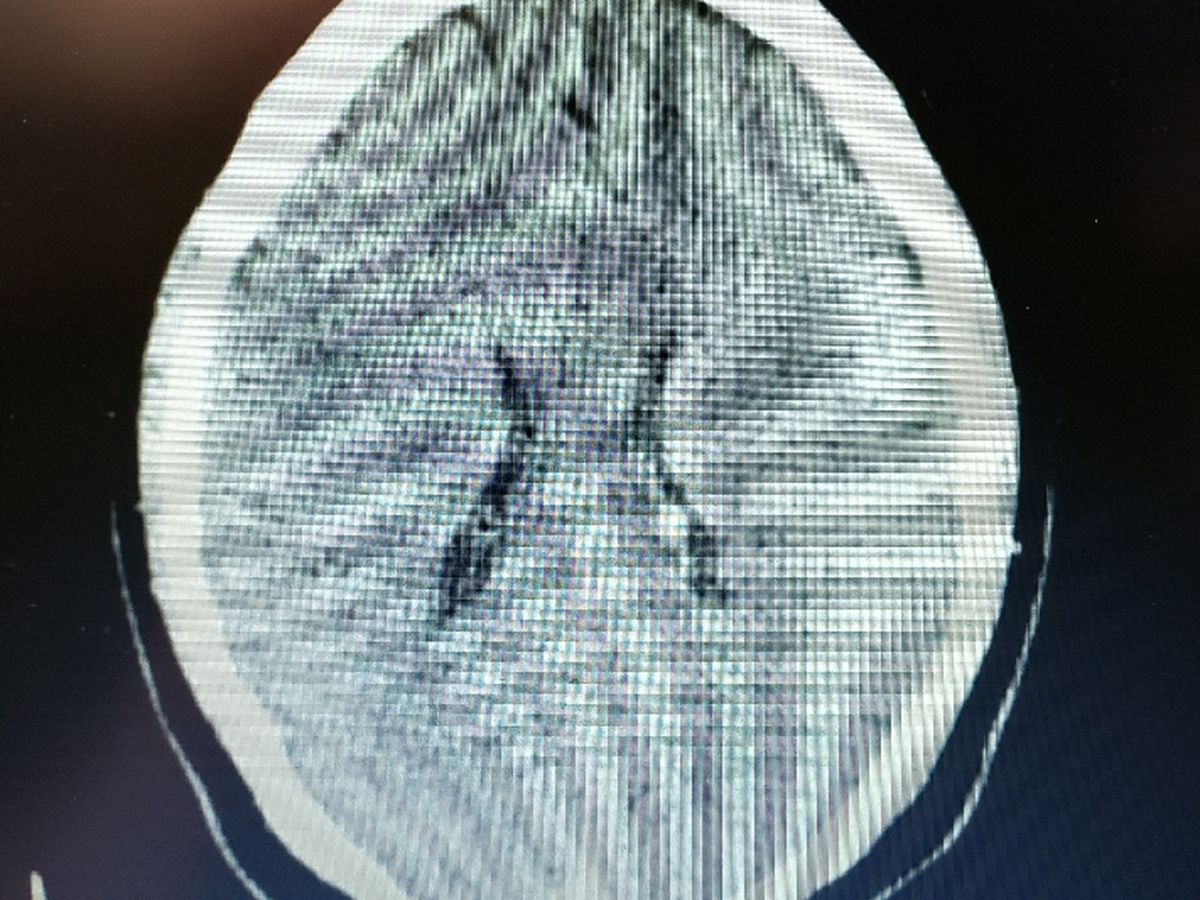

About two months ago I began getting really bad headaches along with high anxiety and waves of confusion. I couldn't figure out what was wrong and why this just started happening and it was getting worse and worse and started affecting my day to day life too much. I went to the hospital and they did a ct scan on my head only to find a cyst in my brain. It is continuing to grow and left unchecked will cause seizures and possibly death. I am unisnured and have gotten denied for medicaid three times already. Already have a bunch of medical bills i can't afford to pay and now can't afford the surgery to have it removed or drained. So I came here to ask for any help anyone can give please. Anything given would be a blessing. Hi, Here's the link to my Venmo profile. Tap or click it, and be sure you're finding my true self.